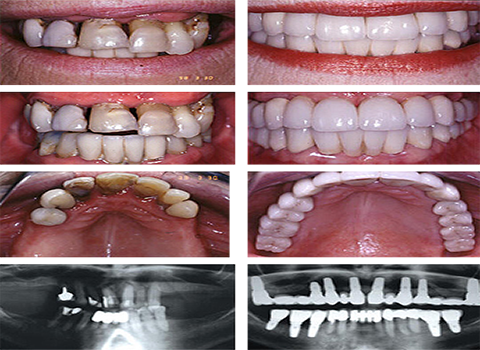

Namman Dental hospital all of your dental needs under one roof and that includes specialists, flexibility in scheduling, inexpensive treatments and much more.

Get yourself treated with some of the best and finest dentists of the city visit our dental hospital.